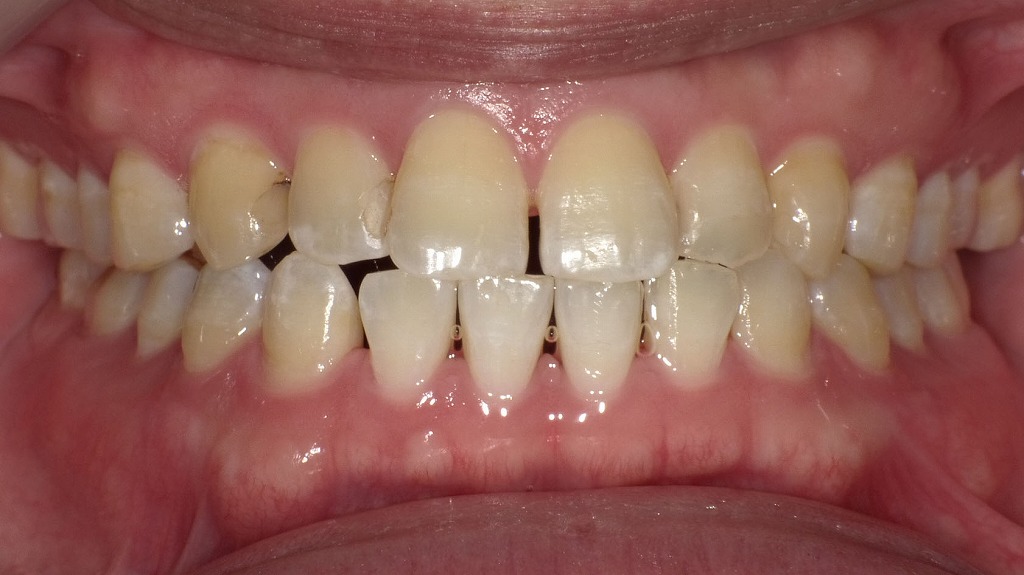

② 歯ぐきの炎症(歯周病・歯槽膿漏)

歯周病が進行すると、歯ぐきの中で膿がたまり、局所的に腫れることがあります。

特に「歯ぐきの一部がぷっくりして痛い」「押すと膿が出る」場合は、歯周病性の腫れが疑われます。

歯面には歯石やプラークが沈着し、歯ぐきには発赤・腫脹がみられます。これは歯周病が進行した状態で、歯周ポケットの内部で細菌が増えることで炎症が悪化し、周囲の組織に膿が溜まると頬が腫れる原因になります。放置すると骨の破壊が進み、歯槽膿漏へ移行することもあるため、早期の治療と専門的クリーニングが重要です。

歯のクリーニング(PMTC)による着色・歯石除去症例

日常の歯みがきでは落としきれない歯石や着色を、専用の器具を用いた歯科クリーニングで除去した症例です。術前では歯の表面や歯の間に歯石やステインの付着が確認されますが、クリーニング後は歯面が滑沢になり、本来の歯の色調に近い自然な明るさを取り戻しています。